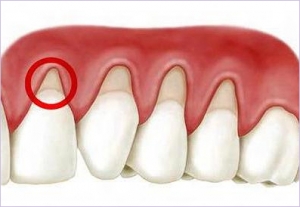

O periodonto é tudo que está em volta do dente: gengiva, ligamento (que segura o dente ao osso) e estrutura óssea. É uma região muito sensível e a qualquer agressão (as mais comuns, a placa e o tártaro) começa a se desorganizar. A gengiva inflama (gengivite) e sangra começando a se afastar do que a agride, se movendo e expondo a raiz do dente. O osso, para não aparecer também foge da agressão, diminuindo a fixação do dente e o deixando com mobilidade.

Caso este processo não seja interrompido podemos perder um dente permanente como se fosse um “de leite”.

Caso este processo não seja interrompido podemos perder um dente permanente como se fosse um “de leite”.

Por tudo isso é de grande importância remover os tártaros com raspagens e um tratamento periodontal. Melhor ainda é evitar este tratamento evitando a placa bacteriana. Fazemos isso com a escovação eficiente após cada refeição e limpezas regulares no dentista para limpar onde a escova não alcançou durante os meses.